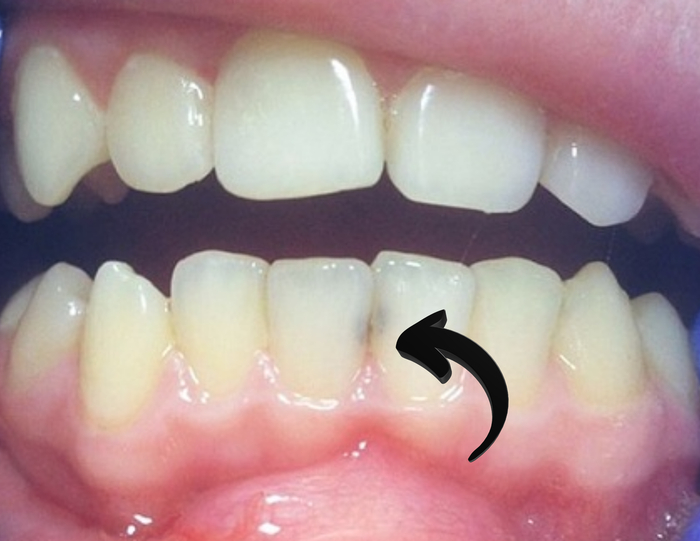

2. Экссудация (пик, как правило, на 3–4‑й день, длится может до 14 дней)

Именно на этой фазе возникает отёк. Из раны может выделяться жидкость(экссудат):